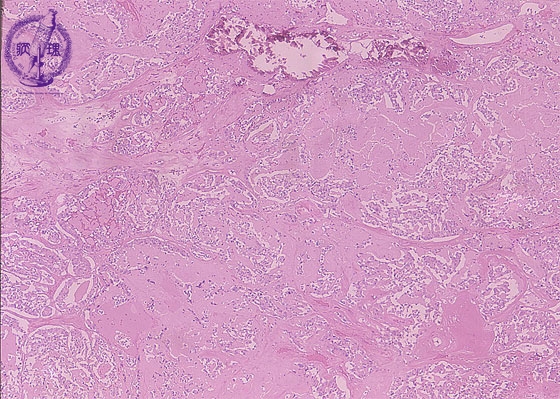

- (10)Medullary carcinoma of the thyroid

Microscopic findings (HE stain, low power view). The tumor cells are arranged in a solid or trabecular architecture. Deposition of amyloid (arrows) and calcification are visible in the tumor stroma.